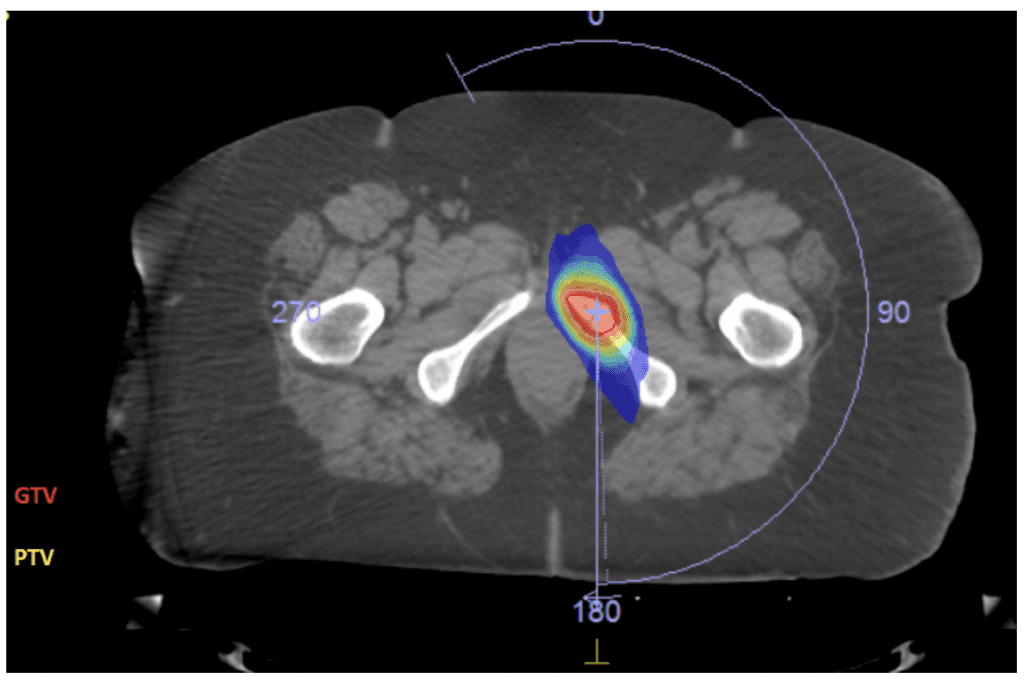

Le premier traitement a été initié en novembre 2017 sur une métastase osseuse. Cette technique est devenue depuis une pratique courante notamment dans les situations oligométastatiques osseuses et ganglionnaires.

Exemple de dosimétrie d’une radiothérapie stéréotaxique d’une métastaste osseuse à Chénieux